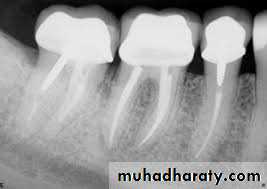

Usually four Photographs can be taken during An Endodontic procedures>

• Initial RadiographDiagnostic

Rdiographs in Endodontics

Show 4-5 mm beyond the apex of the tooth and the surrounding bone or pathologicPresent an accurate image of the tooth without elongation or fore-shortening

Exhibit good contrast so all pertinent structures are readily identifiable.

Requirments of Endodontic Films